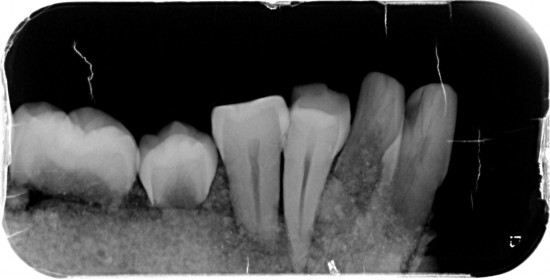

Dit kaakje werd door mijn tandarts grondig bekeken en róntgen foto,s van gemaakt .

Met zijn  langdurige ervaring  uit zijn eigen praktijk. Kunnen namelijk  Molaren verkeerd om zitten. (zie 1ste  molaar linker kaak)

Tevens kunnen er zowel  tanden teveel of te weinig voorkomen .( zie 5 snijtanden ) . De 5de premulaar en hoektand lijken maar een  tand  te zijn , zie rechterkaak. Rontgenfoto wijst echter uit dat het toch 2 aparte tanden zijn .